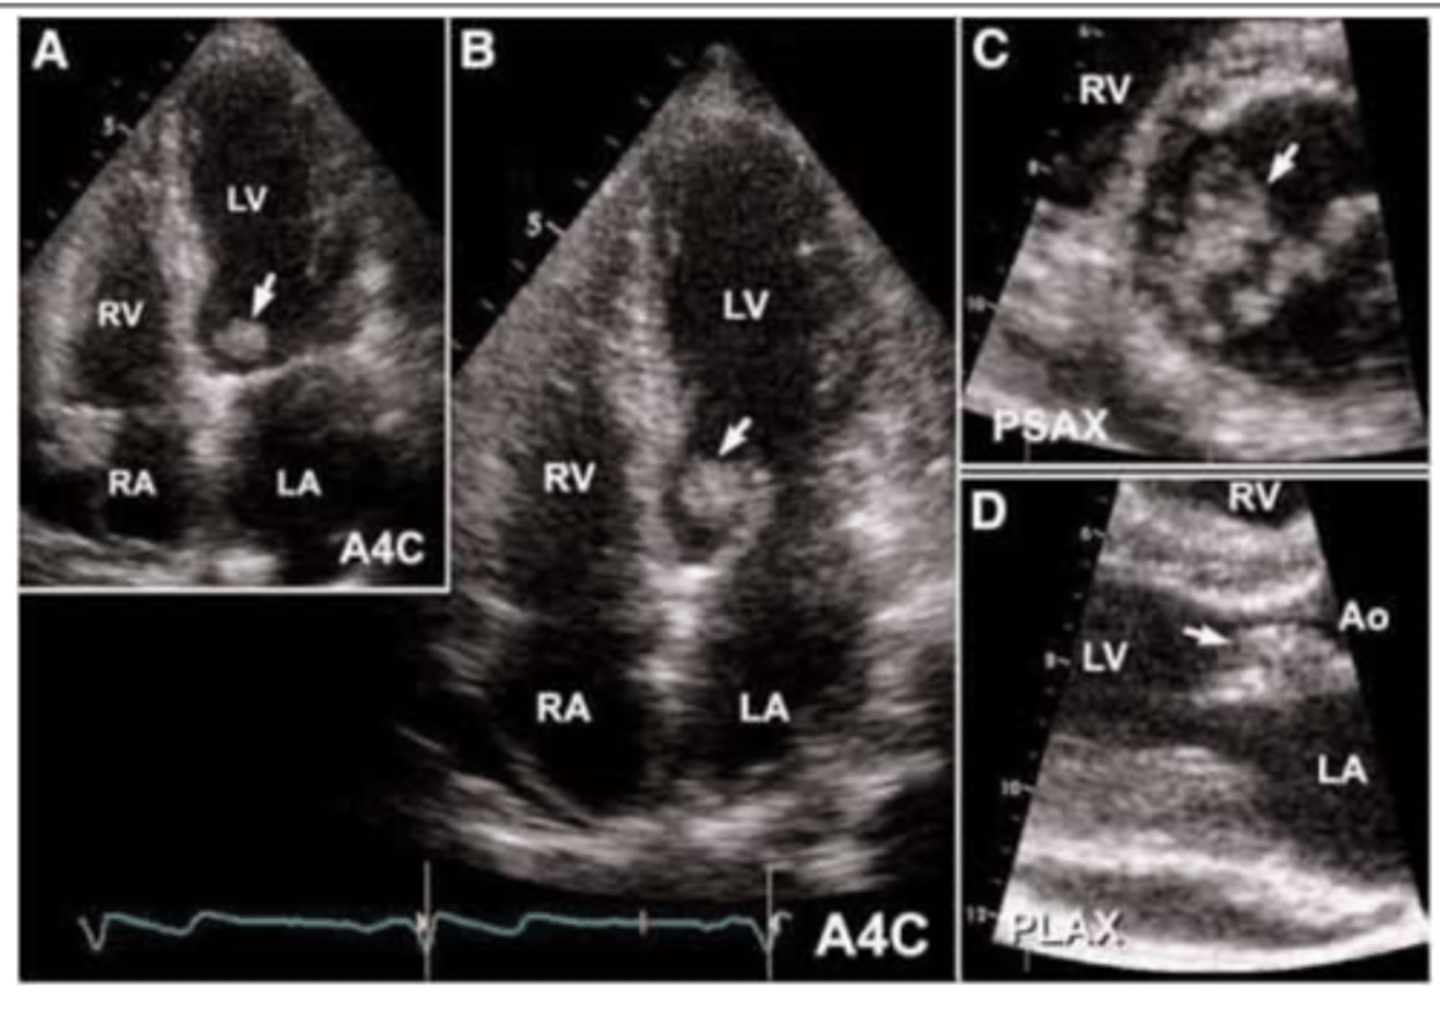

Imaging used to eval endocarditis

Echocardiogram (usually transesophageal)

<p>Echocardiogram (usually transesophageal)</p>